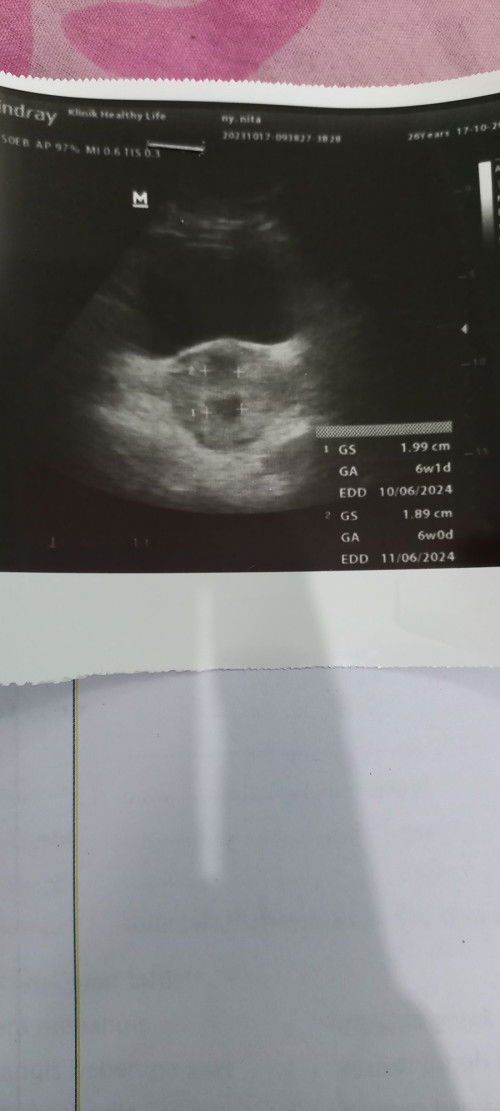

Bunda, mau tanya².. Ini foto USG 1 waktu baru tahu hamil, indikasi 2 kantung hamil (dokter 1) Foto USG 2 baru tadi diambilnya terkonfirmasi janinnya 1 😇(dokter 2) Tadi saya periksa ke obgyn bund, bulan kemarin saya periksa ke bidan sama ke dokter yg faskes. Nah disini bunda² ada yg double periksa kaya saya ke bidan sama ke obgyn jga kah ? Utk obat dan vitaminnya yg di minum hanya dari obgyn saja kan ? Atau gmna ? Mhon sharing nyaa.. Soalnya waktu hamil anak pertama , saya hanya di bidan sajaa bund. #seriusnanya #bantusharing #ingintahu